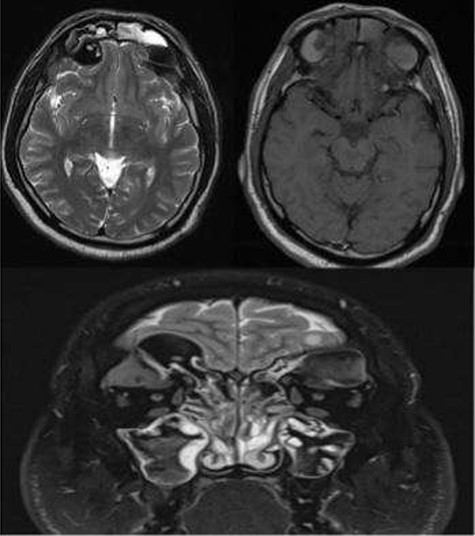

A 35-year-old Saudi male presented to our ENT Clinic with a 1-year history of progressive facial pain, headache, bilateral proptosis, anosmia and nasal obstruction. His past medical history was insignificant. Sinonasal endoscopy revealed multiple bilateral grade IV polyps, occluding the nasal cavities bilaterally. Computed tomography (CT) of the paranasal sinuses showed expansion and remodeling of the frontal sinuses bilaterally (Fig. 1). It is associated with bony dehiscence posterior wall and floor of the sinuses that results in intracranial and intra-orbital extension, respectively. The ethmoid air cells show complete opacification bilaterally with lateral bowing of the lamina papyracea. This along with the frontal sinus orbital extension lead to the clinical presentation of the orbital proptosis. The maxillary antra disease results in remodeling of the stomatal complex and obliteration of the superior two-thirds of the nasal cavities. The contents of the sinuses show mixed iso and hyperdense material. Magnetic resonance imaging (MRI) of the paranasal sinuses demonstrates the orbital and intracranial extension of the disease with no invasion of the adjacent tissues or brain parenchyma (Fig. 2). The hyperdense contents show marked low signal intensity on T2 and high signal intensity on T1.

MRI paranasal sinuses axial and coronal T2 and axial T1 The MRI shows the expansion with the remodeling of the sinuses and intra-orbital/intracranial extension. The hyperdense contents show marked low signal intensity on T2 and high T1 signal. No tissue invasion of the orbital or brain parenchyma.